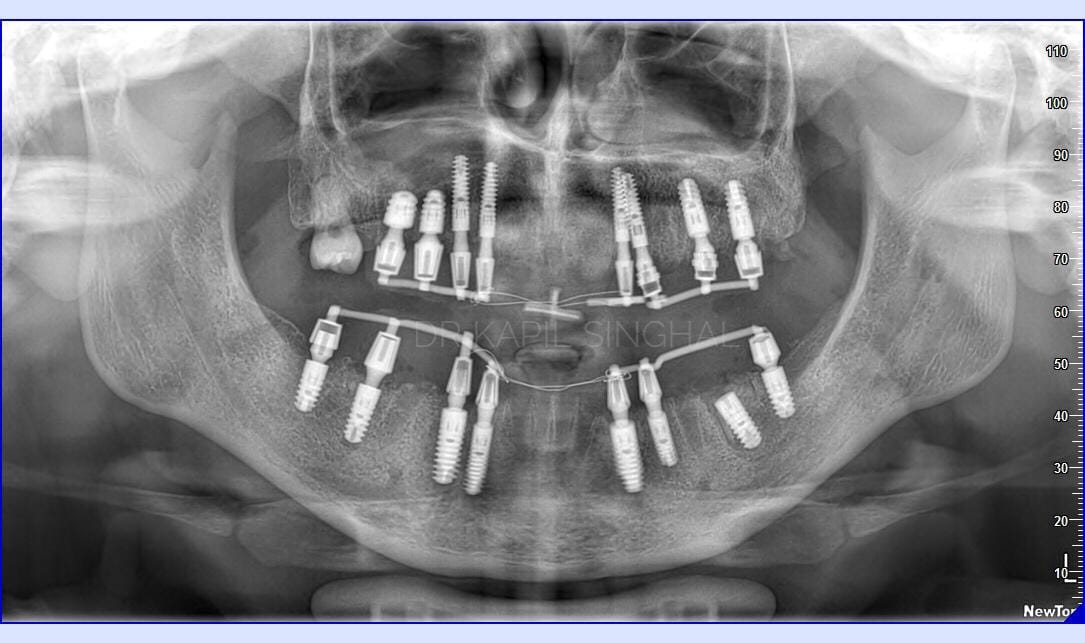

Immediate implants In a 27 year old boy ..Intraoral Welding and conometric fitted immediate prosthesis

This case demonstrates the importance of placing immediate dental implants in the correct prosthetic position